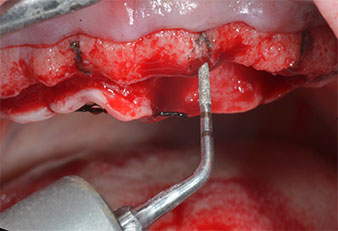

Ein flammenförmiges, diamantiertes piezochirurgisches Instrument (Piezomed I1) wurde verwendet, um die Implantatpositionen zu markieren und die Pilotpräparationen durchzuführen (Abb. 3). Dabei wurde darauf geachtet, eine Auf- und Abbewegung mit reduzierter Leistung, voller Spülung und niedrigem Druck (unter 300 g) anzuwenden. Als Nächstes wurde ein Pilotinstrument (Piezomed I2A/I2P) zur initialen Erweiterung der Implantatlager auf einen Durchmesser von 2 mm verwendet (Abb. 4), gefolgt von einem 3-mm-Instrument (Abb. 5).

Bei dichtem Knochen sollte das gesamte Set, einschließlich der Zwischeninstrumente Piezomed Z25P und Z35P verwendet werden, um die Osteotomien vor dem nächsten Schritt zu erweitern.

Diese Instrumente sind auch für die Aufbereitung bei interner Sinusbodenaugmentation in der Nähe der Sinusmembran indiziert oder wenn weniger als 4 mm Restknochenhöhe verbleibt.

Im vorliegenden Fall wurden die Instrumente Z25P und Z35P wegen des relativ weichen posterioren Knochens nicht verwendet, der problemlos mit dem I3A/I3P bearbeitet werden konnte.